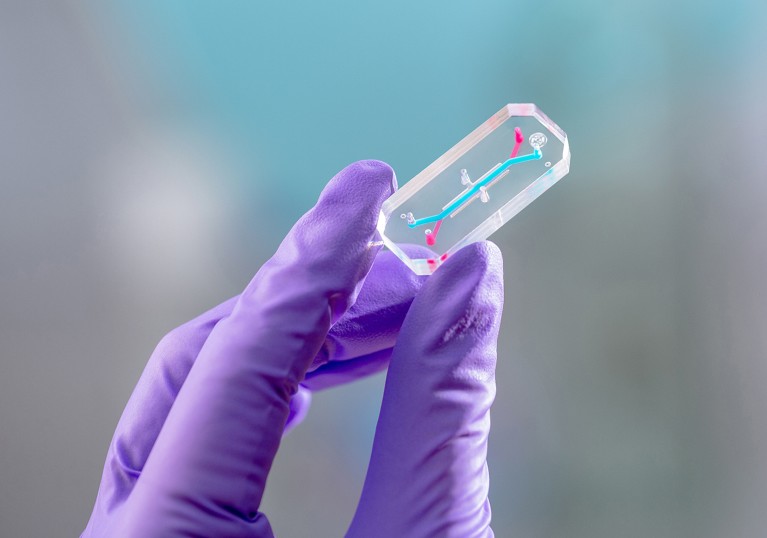

But perhaps the most cutting-edge human-health study that will be conducted during Artemis II is an ‘organ on a chip’ experiment. For this, researchers asked each of the astronauts to donate platelets from blood before the space flight. From those donations, scientists extracted, isolated and froze immature bone marrow cells, which naturally circulate in people’s bloodstreams. Just before launch, the researchers plan to thaw and place the cells onto two chips, about the size of a USB drive, for each astronaut. One chip will fly aboard Artemis II, and the other will remain on Earth for the mission’s duration.

Researchers will place cells from each Artemis II astronaut onto an ‘organ on a chip’ to test their reaction to deep-space radiation during the flight.Credit: Emulate/NASA

Once the flight is over, researchers will compare both chips for each crew member to see if the cells that flew in space experienced more DNA damage, changes to telomere length or other signs of alteration owing to space flight2. That information can then be linked back to the particular astronaut and their health. “It’s the first time this has been done, and it’s all being done outside of low Earth orbit,” says biomedical scientist David Chou, the principal investigator for the organ-on-a-chip experiment at biotechnology company Emulate in Boston, Massachusetts.

If successful, such chips could help to protect astronauts in the future: NASA could simply fly chips containing cells from a potential astronaut into deep space to understand what might happen to them if they took such a journey.